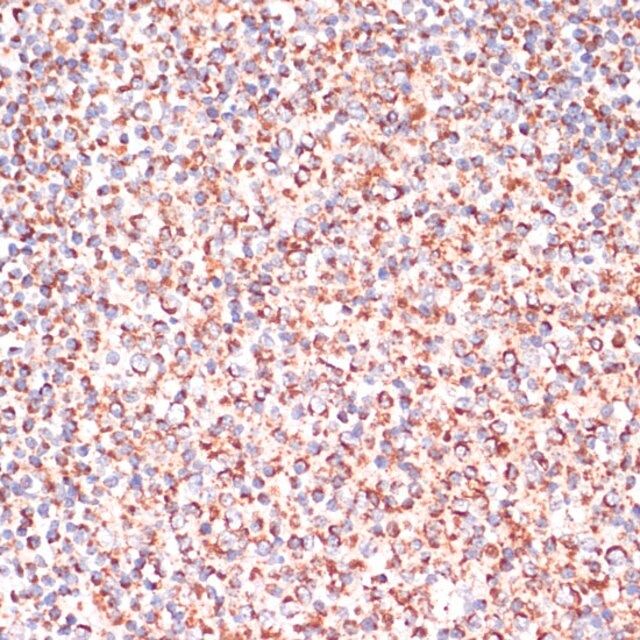

| technique(s) | immunofluorescence: 1:50-1:200 immunohistochemistry: 1:50-1:200 western blot: 1:500-1:2000 |